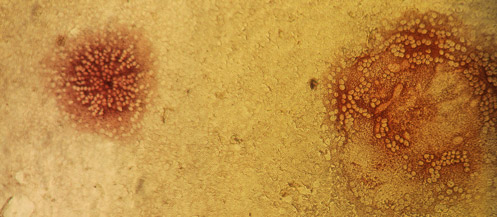

Cells infected with canine distemper virus fuse to neighboring uninfected cells to form syncytia. Antibodies against canine distemper virus are used to stain the infected cells with a red dye

Source: PEI

Cells infected with canine distemper virus fuse to neighboring uninfected cells to form syncytia. Antibodies against canine distemper virus are used to stain the infected cells with a red dye

Source: PEI